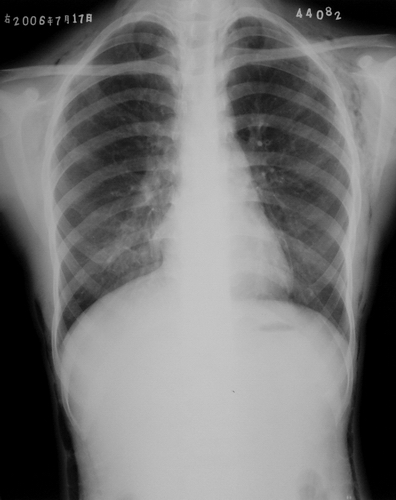

左侧胸壁、腋窝、颈部及右侧颈部皮下软组织内示斑片状、条状低密度气体影,四天后复查片明显吸收好转。